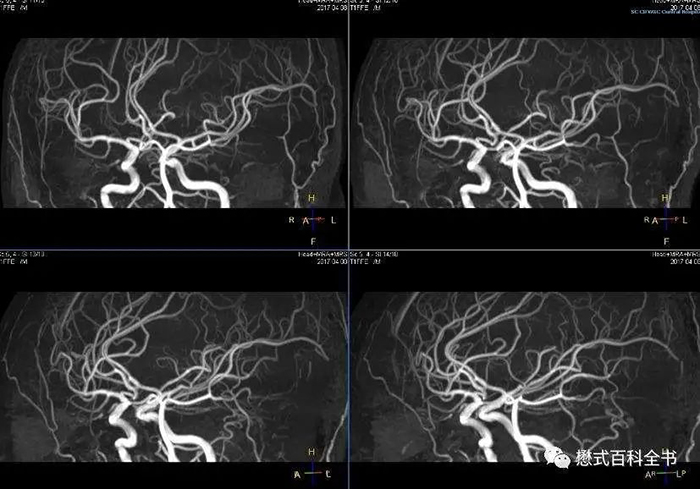

定期进行血管的筛查

血管筛查主要包括:颈部血管彩色多普勒超声、经颅多普勒超声(TCD)、磁共振血管成像(MRA)、CT血管造影术(CTA)、数字剪影血管造影术(DSA)等。颈部血管超声、经颅多普勒超声(TCD)是卒中筛查最基本、最便捷的无创性检查,可及时检出血管病变,为预防脑卒中争取时间和机会。因此,专家建议,60岁以上或有多种脑血管病高危因素的人,应每年进行脑血管的检查,并注意定期复诊,动态观察血管情况。